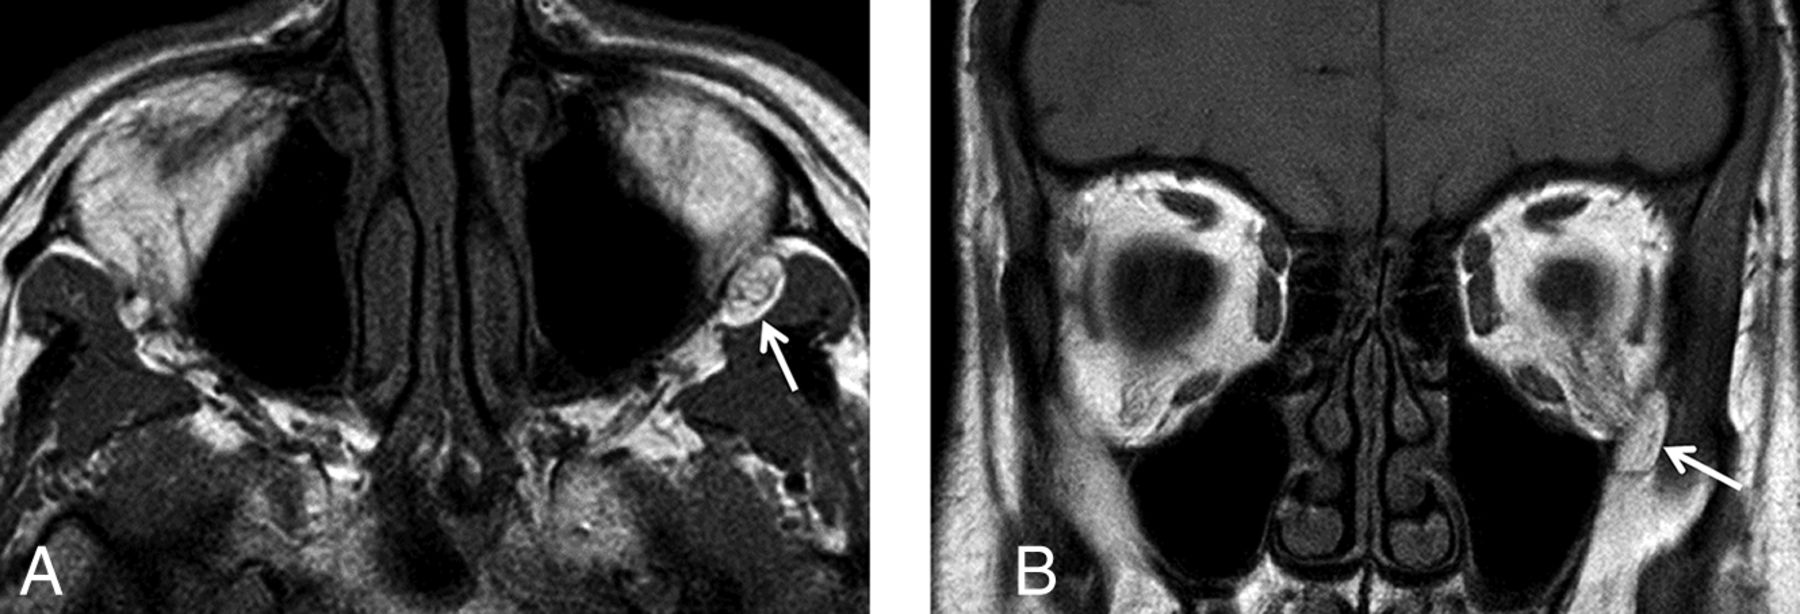

Prolapse was defined as present when a discrete, rounded focus of fat signal intensity could be identified as both distinguishable from the normal infratemporal fossa fat and contiguous with the normal orbital fat via the inferior orbital fissure (Fig 1). When prolapse was present, 1 fellowship-trained neuroradiologist performed a long-axis measurement of the prolapsed fat on high-resolution T1 images. The same neuroradiologist also evaluated the prolapsed fat for associated septa on T1-weighted images, fluid signal on STIR images, and enhancement on gadolinium-enhanced T1-weighted images with fat suppression (Fig 2). Additionally, a different neuroradiologist measured the perpendicular distance from the anterior margin of each globe to the interzygomatic line with the upper limit of normal defined as 21 mm7 and the lower limit of normal defined as 12 mm.8

Axial (A) and coronal (B) T1-weighted images demonstrate prolapse of the left orbital fat (white arrows) into the left infratemporal fossa via the left inferior orbital fissure.